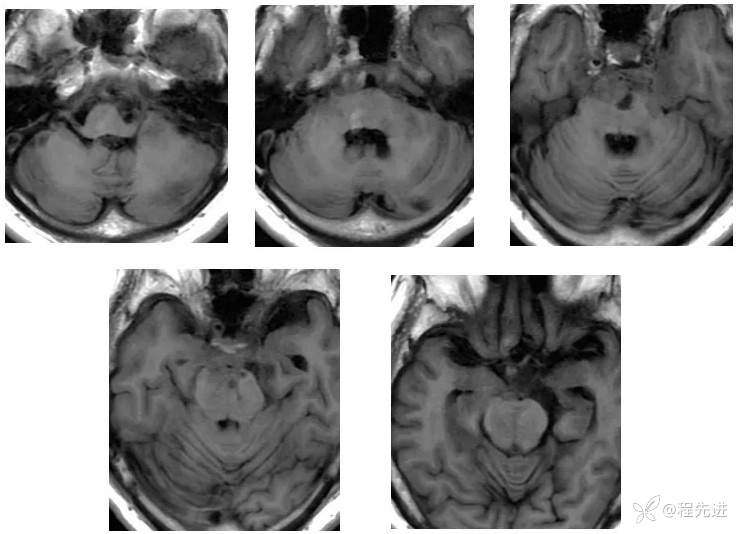

【现病史及既往史】:右眼斜视及视力下降7个月,右眼脸下垂3个月,右眼失明1个月

查体:生命体征平稳,右眼脸下垂,右眼失明,左眼内收位,外展受限,光反应迟钝,左侧角膜反射减弱,左侧听力下降,左面部痛温觉减弱无吞咽困难,无饮食饮水呛咳,伸舌舌尖左偏。